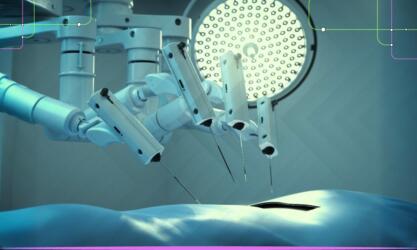

في السنوات القليلة الماضية، أظهرت الأبحاث أن أداء التعلم العميق يمكن أن يضاهي أداء الخبراء في مهام التصوير الطبي مثل…

تدفع جائحة كوفيد-19 موارد المستشفيات إلى حافة الانهيار في العديد من دول العالم. لذا، فلا عجب في أن يأمل الكثيرون…